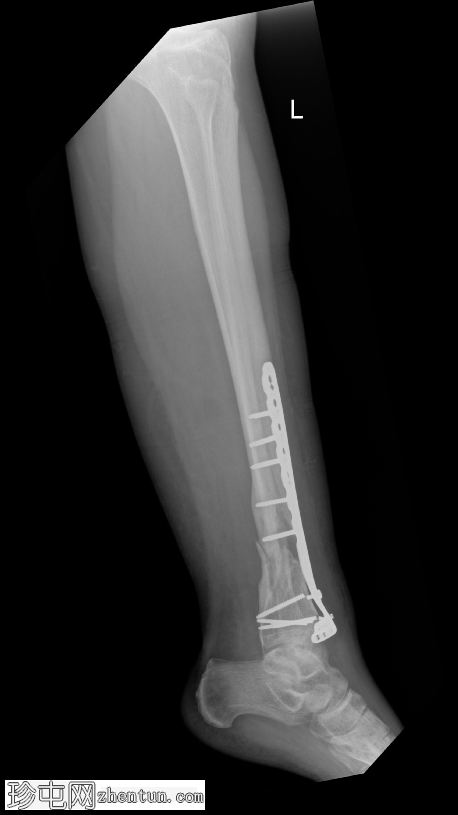

侧位片

2.png

可见胫骨远端前内侧支撑钢板,并有多枚螺钉固定,与既往胫骨远端骨折切开复位内固定术(ORIF)相符。

数枚远端螺钉断裂,钢板远端与胫骨远端骨膜表面分离,提示钢板与骨骼接触不良,可能存在内固定松动或部分机械失效。其余螺钉及钢板近端部分完整,对位良好。

胫骨远端内侧可见一小块骨化良好的骨碎片,密度与邻近骨皮质相似,提示为既往骨折残留碎片,而非急性骨折碎片。

骨折部位显示部分愈合,胫骨和腓骨整体对位良好。踝关节间隙保持正常。未发现新的骨折、脱位或骨膜反应。

无既往X线片可供对比。